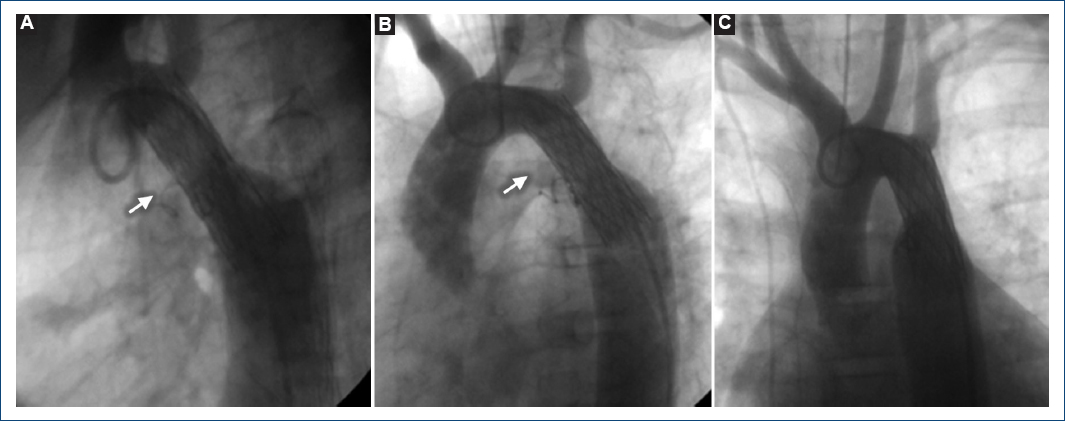

Figura 2 A-C: angiografía en el arco aórtico. Se observa resolución completa de la coartación aórtica con un stent desnudo (Palmaz 4014) y cierre del conducto arterioso con un coil (flecha).

Paciente de sexo femenino de 7 años 11 meses de edad con clase funcional I, asintomática cardiovascular, sin otros antecedentes patológicos no cardiovasculares de importancia. Exploración física: 28 kg, frecuencia cardiaca 82 x', frecuencia respiratoria 28 x', tensión arterial miembro torácico derecho 130/80 mmHg, miembro pélvico derecho 80/60 mmHg, saturación de oxígeno 93%. Campos pulmonares normales, ruidos cardiacos rítmicos, IIp normal, soplo sistólico II/IV paraesternal izquierdo alto con irradiación a la espalda, sin chasquido protosistólico, ritmo de cuatro tiempos, hígado normal, pulsos ausentes en miembros inferiores, no cianosis, no hipocratismo. Electrocardiograma: ritmo sinusal, frecuencia ventricular media 80 x', eje de QRS + 10, PR corto y onda delta, QRS 100 ms (haz lateral derecho). Radiografía de tórax: situs solitus, sin cardiomegalia, flujo pulmonar normal. Ecocardiograma: situs solitus, conexión atrio-ventricular y ventrículo-arterial concordantes, sin comunicación interauricular ni foramen oval permeable, porción atrializada del ventrículo derecho del 40%, con insuficiencia tricuspídea leve, presión sistólica de la arteria pulmonar (PSAP) 30 mmHg (Fig. 1A y B); además como lesiones asociadas se encontraron CoAo yuxtaductal con gradiente máximo de 68 mmHg y persistencia del conducto arterioso (PCA) con extremo pulmonar de 2 mm con cortocircuito de izquierda a derecha. Cateterismo cardiaco: CoAo yuxtaductal con gradiente pico a pico de 40 mmHg con leve hipoplasia del istmo aórtico, PCA con extremo pulmonar de 1.3 mm, PSAP de 24 mmHg, sitio de coartación con una luz de 4.1 mm, istmo aórtico 9.7 mm (Fig. 1C). Se canuló conducto arterioso por vía retrógrada, se realizó un asa arterio-venosa, se cerró el conducto arterioso por vía anterógrada con coil PDA 4 asas x 5 mm (Cook®) y posteriormente se realizó aortoplastia con stent Palmaz 4014 (Johnson & Johnson®) montado en un catéter bibalón 6-12 x 40. Angiografía de control: stent en buena posición sin gradiente residual, sin zonas de disección y cierre del conducto arterioso (Fig. 2), no se presentaron complicaciones. Posterior al intervencionismo presentó preexcitación intermitente que desapareció a las 24 horas. Se egreso a las 36 horas sin complicaciones. Seguimiento a 14 años: sin eventualidades en clase funcional 1 de la New York Heart Association (NYHA) y ecocardiograma transtorácico con gradiente residual máximo de 18 mmHg y medio de 10 mmHg a nivel del istmo aórtico.